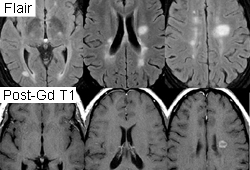

MRI brain scan with gadolinium is used when the diagnosis of multiple sclerosis is being considered. A lumbar puncture and cerebrospinal fluid analysis (including a differential cell count, culture, and serology) should also be performed, along with an evoked potentials test, if multiple sclerosis is suspected. Lumbar puncture and cerebrospinal fluid analysis should be performed if encephalitis is suspected and a mass lesion in the brain has been excluded. CT scan of the chest is useful to diagnose thymoma following a chest x-ray. [Figure caption and citation for the preceding image starts]: MRI using FLAIR and contrast agent gadolinium showing typical lesions seen in MS in the periventricular regions.From the personal collection of Lael A. Stone, Mellen Center for MS Treatment and Research, Neurological Institute, Cleveland Clinic Foundation; used with permission [Citation ends].